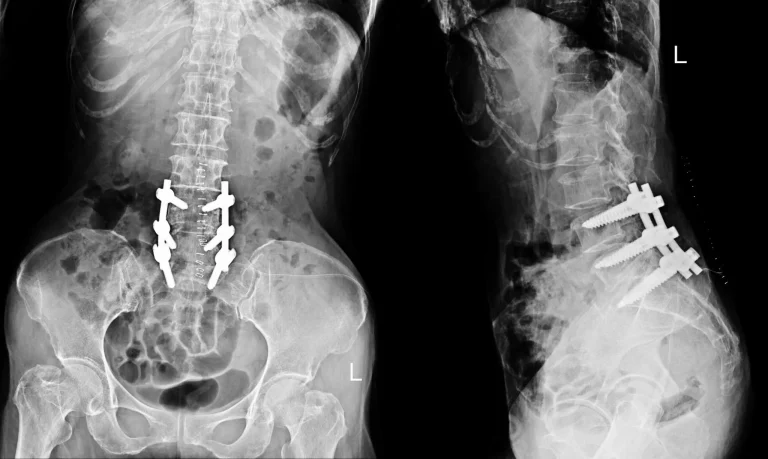

MRI of the spine showing bone slip due to post-surgical instability, indicated by red arrows.

Spinal Instability

Bone destruction from the procedure causes vertebral instability requiring fusion with screws and rods.